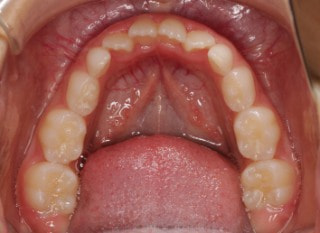

小児期第二段階

開始時